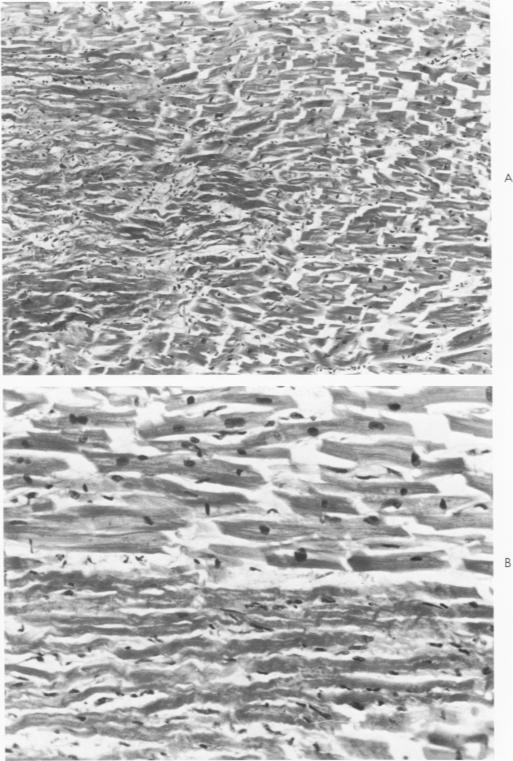

The histopathology of human myocardial infarcts is reviewed in a series of 46 cases ranging from sudden death to a clinical age of 3 days. A set of histopathologic features is described whereby the diagnosis of acute myocardial infarction can be made, even in cases of sudden death, on routine sections and even after considerable autolysis. This is primarily a stretching and waviness of the myocardial fibers, especially at the border of the infarcted area. Its mechanism is probably twofold: the rythmical pull exerted by the normal myocardium against the infarcted paralyzed area and the outward bulging of this area at every systole. On the basis of human material alone, it may be inferred that this pattern develops very rapidly: surely less than 1 hour and perhaps a few minutes after the local circulation has failed.

回顾了46例人类心肌梗死的组织病理学情况,这些病例涵盖了从猝死到临床病程3天的患者。描述了一组组织病理学特征,据此即使在猝死病例中,通过常规切片,甚至在经历相当程度的自溶后,也能够作出急性心肌梗死的诊断。这主要表现为心肌纤维的伸展和波纹状,特别是在梗死区域的边界处。其机制可能是双重的:正常心肌对梗死的麻痹区域施加的节律性牵拉,以及该区域在每次心脏收缩时向外膨出。仅基于人体材料就可以推断,这种形态发展非常迅速:肯定在局部循环停止后不到1小时,也许几分钟内就会出现。